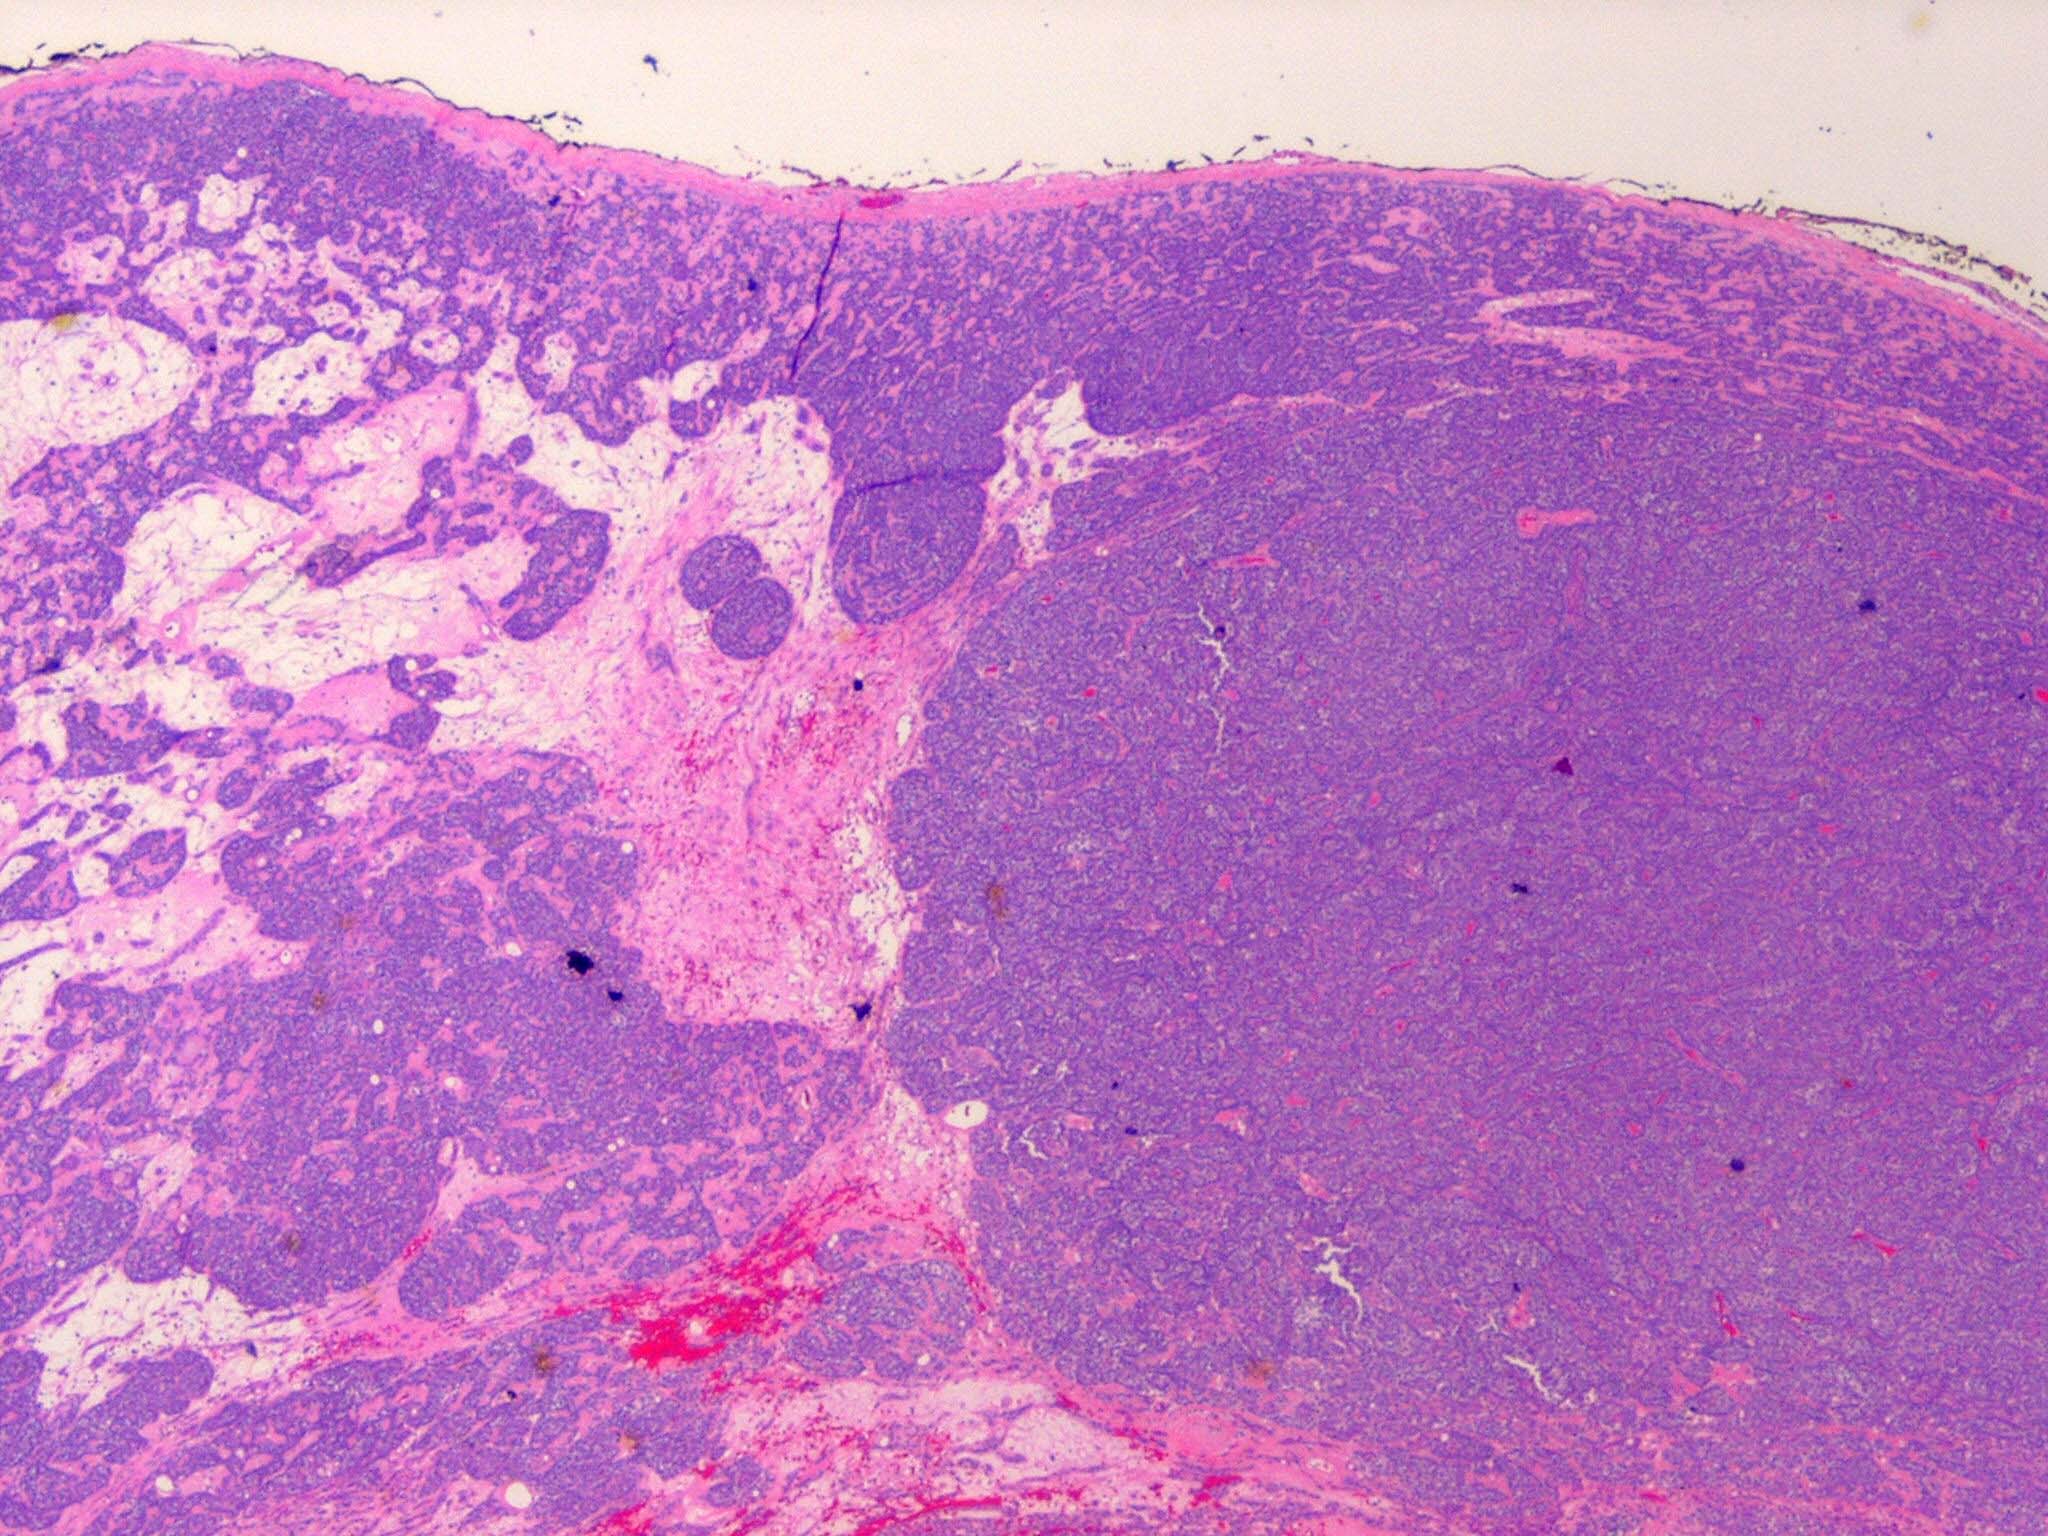

Spiradenoma=ورم غدي عرقي